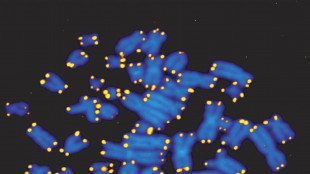

L'invecchiamento del Dna alla base dell'Alzheimer, lo studio italiano

Centrale il danneggiamento dei telomeri, si aprono nuove prospettive terapeutiche